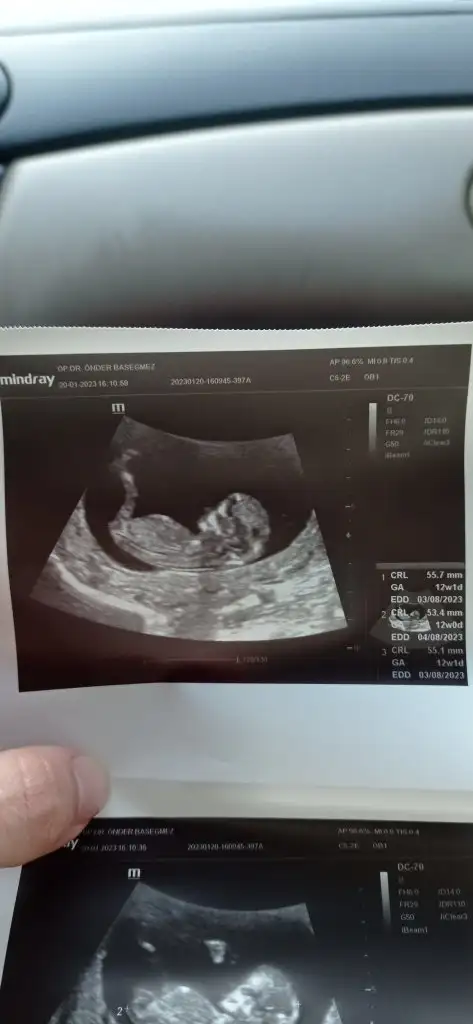

Nub,skull ve cinsiyet

bana da bakar mısınız ☺️

• IMG_20230120_162525.webp

IMG_20230120_162525.webp

16,8 KB · Görüntüleme: 90